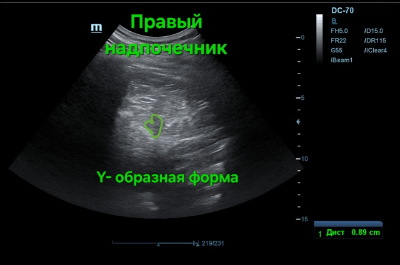

Как правило, при УЗ-сканировании надпочечник имеет треугольную/Y-образную, лентовидную, реже серповидную или конусовидную форму.

Корковое вещество гипоэхогенное, а мозговое по эхогенности выше.

Многие авторы считают, что измерение нескольких параметров (длина, ширина и т.д.) неизменённых надпочечников некорректно, более объективным показателем служит толщина надпочечника (точнее, его «ножек» в зависимости от формы), которая составляет в норме до 10 мм.

Академическая УЗ-картина нормальных надпочечников представлена на фото ниже.

Фото 2 — Правый надпочечник